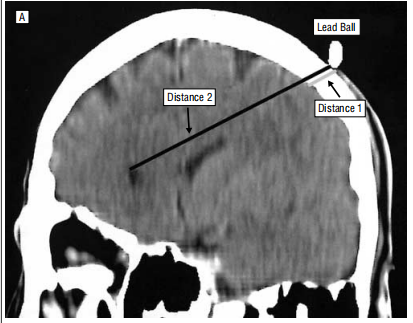

現有TMS范式,大多由較年輕的大腦模型研究而成,沒有考慮到年齡相關性的腦萎縮對TMS治療的影響,與年齡有關的腦萎縮可能導致線圈與腦組織之間的距離增加,以及腦脊液增加,從而影響TMS脈沖產生的電流的傳播。也有研究表明,頭皮與額葉皮層之間的距離越大,則rTMS治療老年抑郁患者的臨床療效越低。

圖1:研究表明,老年人前額葉皮質萎縮明顯。頭皮與額葉皮層之間的距離越大,則rTMS治療老年抑郁癥的臨床療效越低。